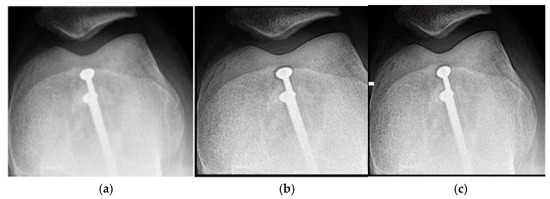

Wrist radiographic images processed with values close to d = 1.4 (Figure 7) show greater sharpness and detail, as in the case of the knee. The contrast improves steadily up to d = 1.4, as shown in Table 4. Entropy increases slightly, maintaining noise levels. The maximum contrast value is 3.76 at d = 4.4, which is a 38% improvement. Visual inspection confirms that the filter works in small, highly detailed regions.

Figure 8 and Figure 9 present the behavior of contrast and entropy for wrist images as a function of d. In the graph, Filter 1: Cream (red) and Filter 2: Bosso (blue). These figures demonstrate the effectiveness of the double filter in enhancing wrist X-rays.

Figure 8 improves the contrast in wrist imaging are quantified, demonstrating a superior response of 38%. This significant enhancement in image quality allows for the better visualization of wrist anatomy and pathologies, thereby aiding in more accurate diagnoses and effective treatment planning [10].

Figure 9 shows that a progressive improvement in the structural information captured in wrist imaging is documented. This highlights significant advances in image quality, allowing for more detailed and accurate assessments of wrist anatomy and pathologies, which are essential for effective diagnosis and treatment [13].

Table 4 shows the contrast and entropy values for different d values in the wrist image. As with the knee image, both filters achieve an increase in contrast, with a crossing of the curves earlier than in other cases. Entropy also presents an ascent but maintains reasonable values.

Figure 7. Original image (a) obtained from the wrist for d = 1.4, with filter 1 (b) and filter 2 (c).